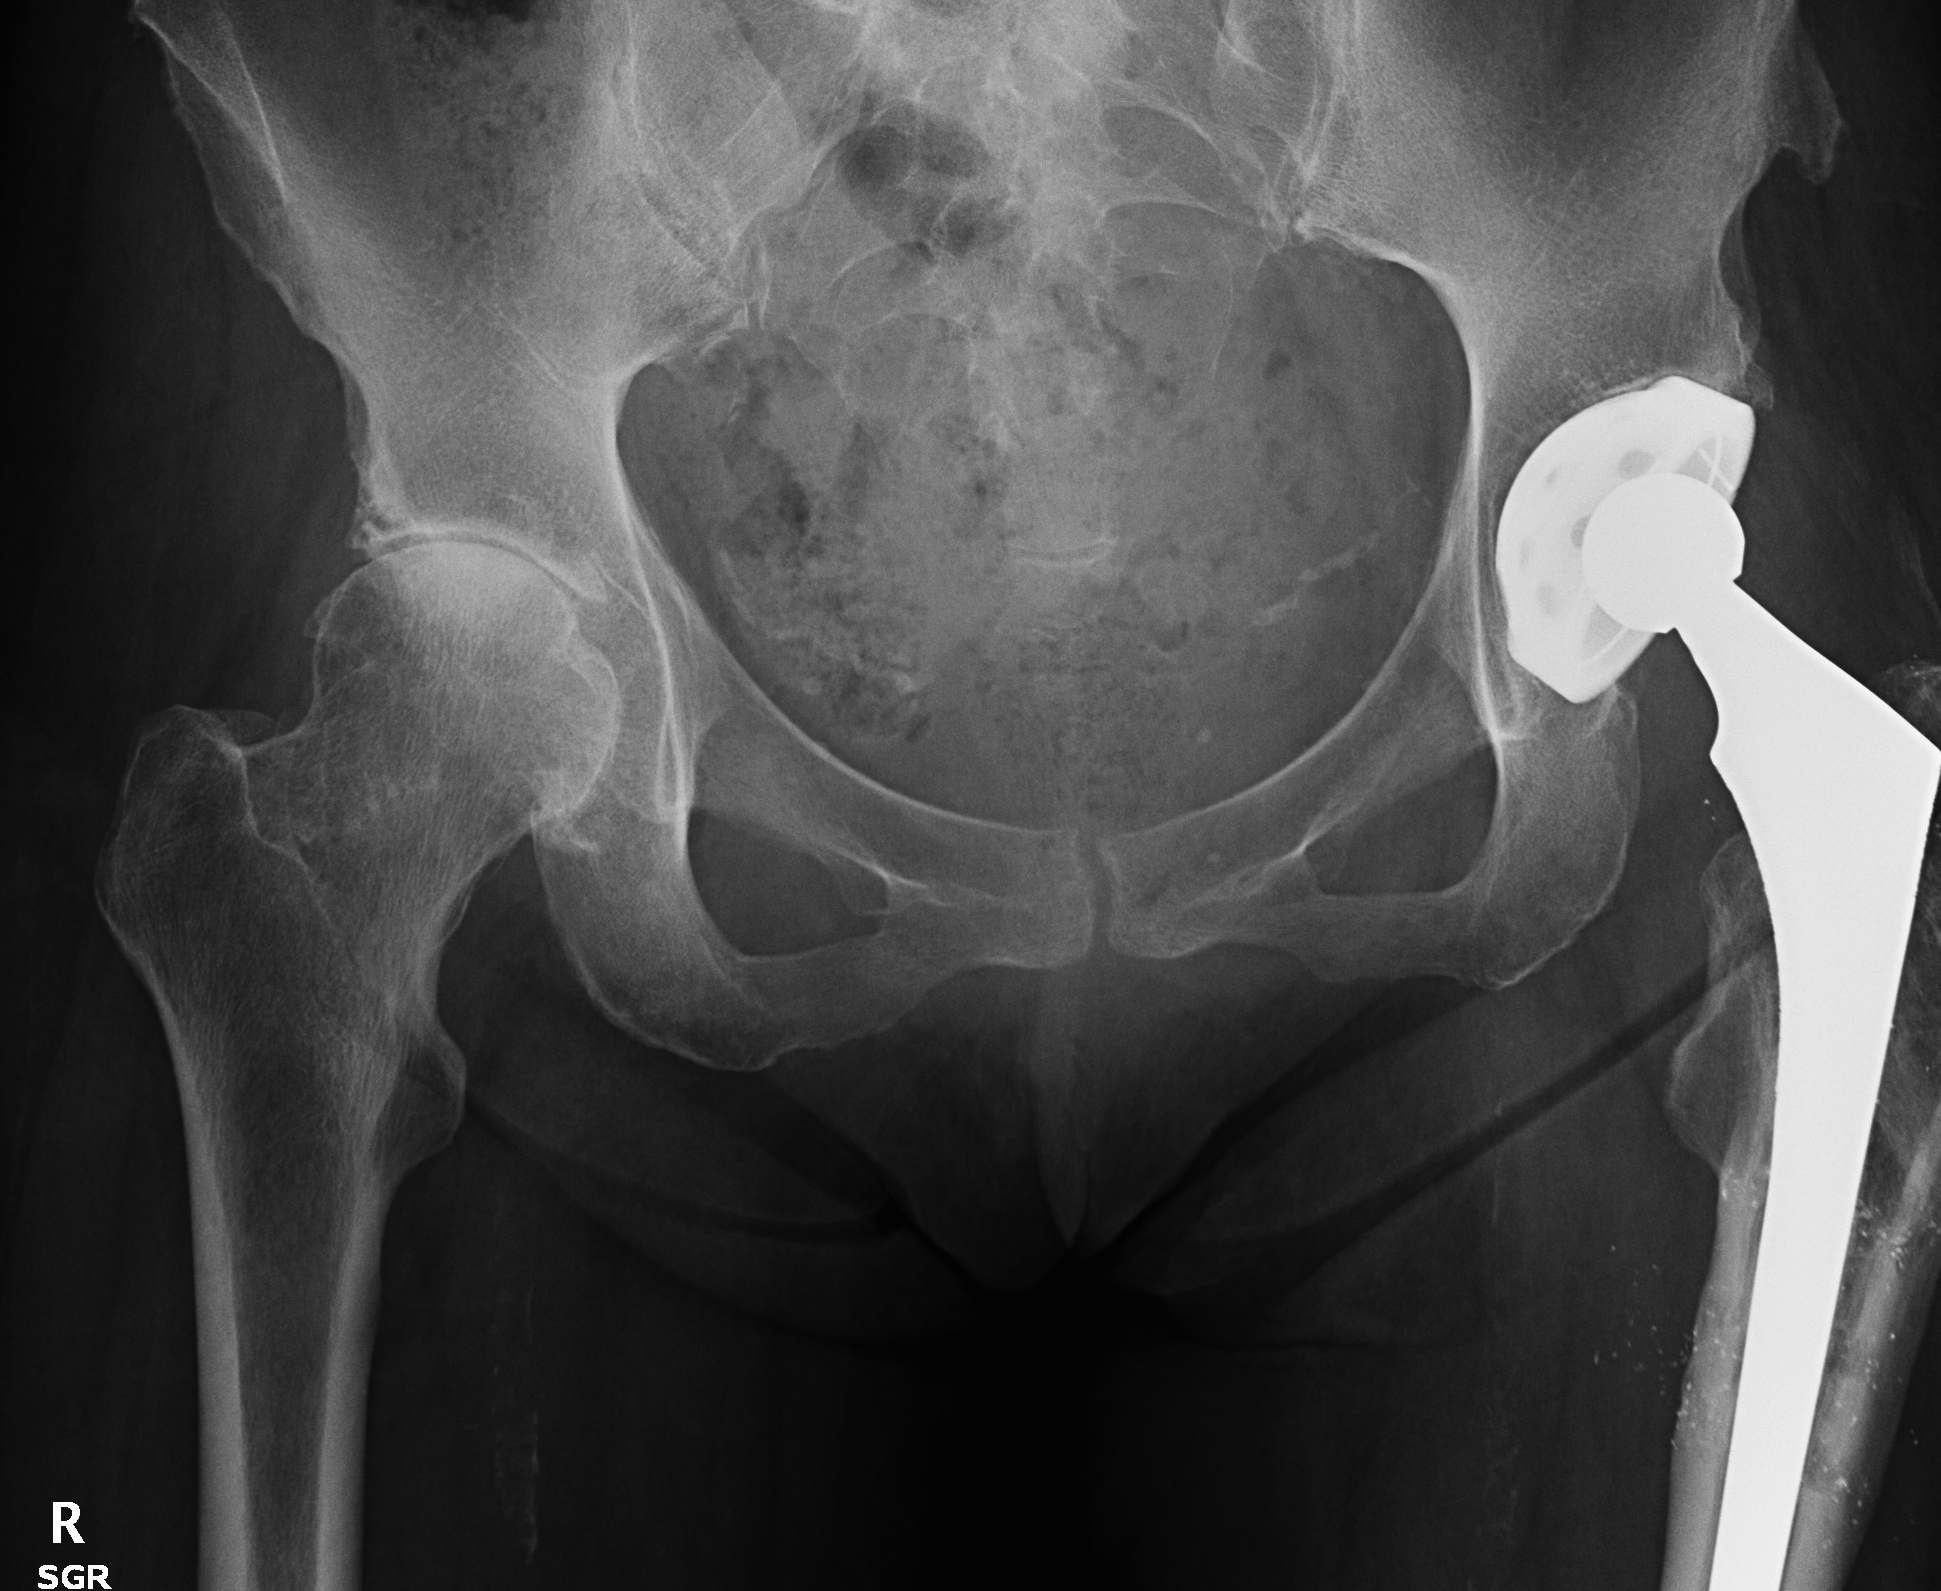

6. Eccentric liner wear

7. Loosening

Loose acetabular components